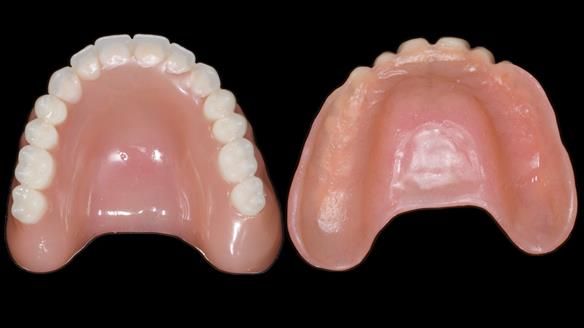

In this edition, I present the complete denture treatment for Kate, a 69-year-old American woman living in Garstang, UK. Kate had been edentulous for many years and required a set of complete dentures that closely mimicked her natural teeth. The new upper and lower dentures provided excellent retention and stability, with significant suction in the upper denture. Below, I detail the step-by-step process of her treatment, as well as my workflow for implant-supported overdentures for patients who may require them.

Treatment Process: I provided the clinical work while Rowan Garstang and Sam Hesketh delivered the technical aspects. The treatment required fifteen visits to fit and review Edgar.